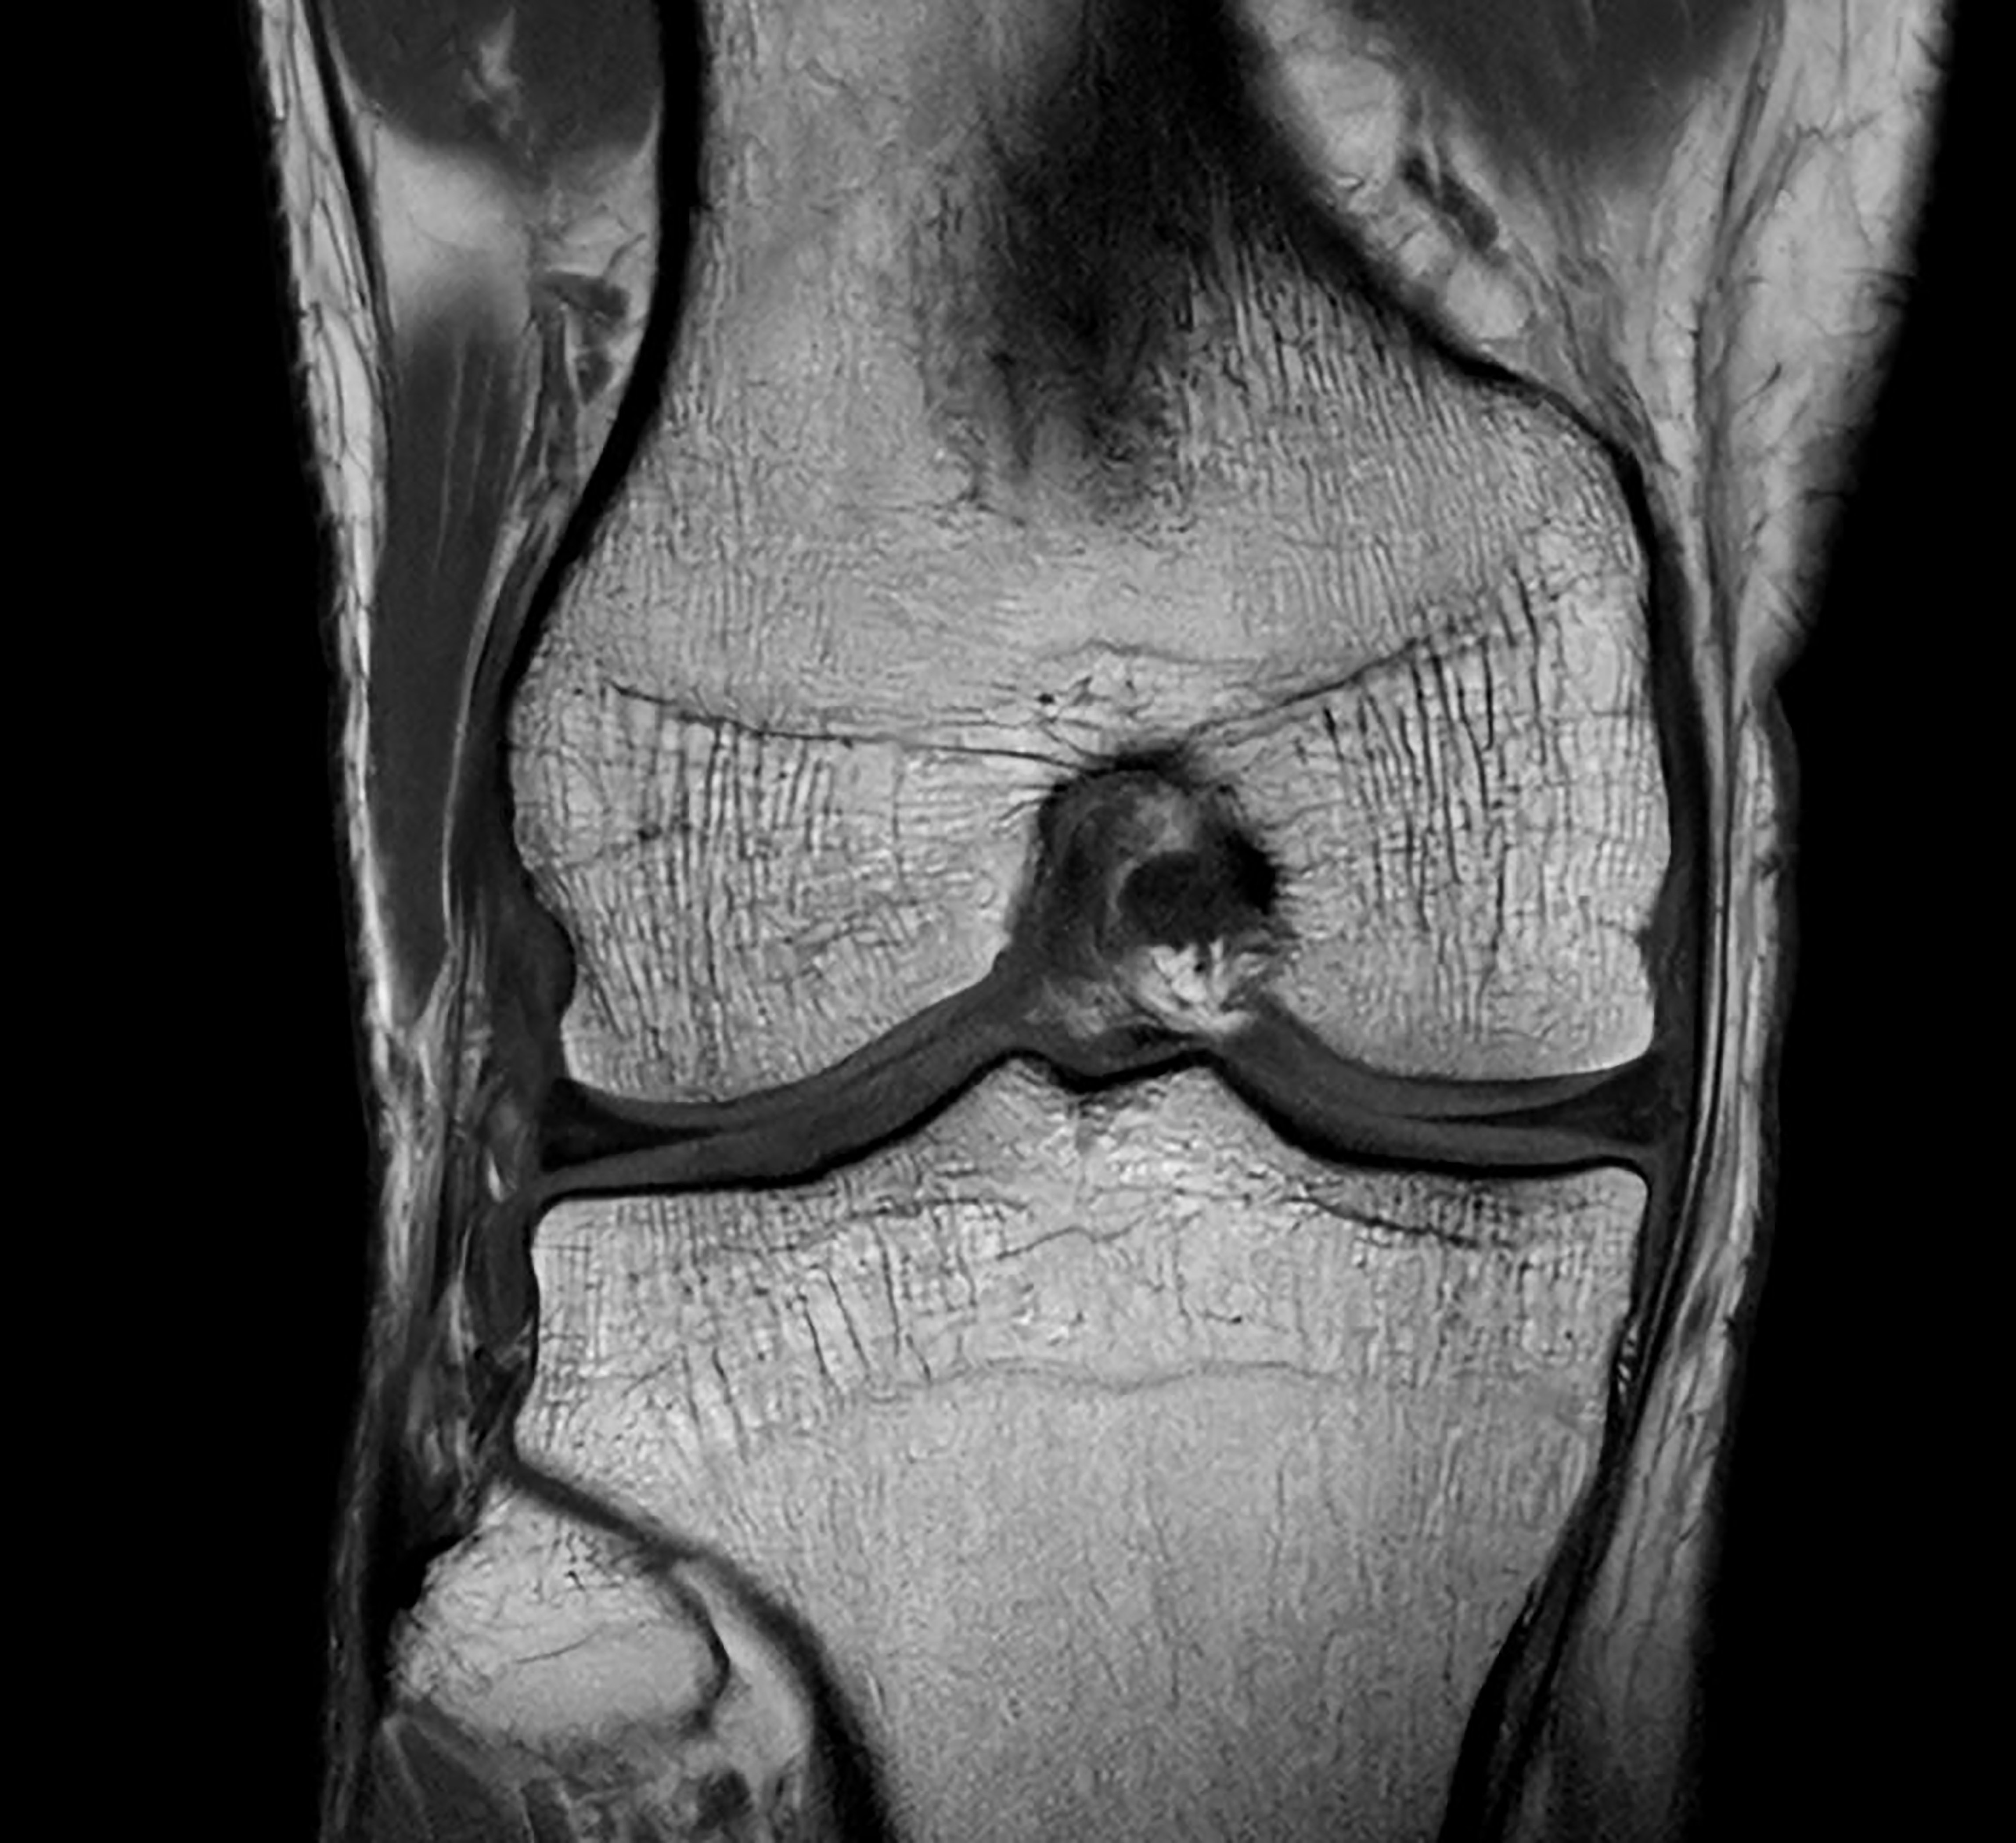

Customers also anticipate significant time savings and workflow improvements with Philips’ dual-AI SmartSpeed Precise [1] technology, which helps streamline their imaging processes, enhance efficiency, and increase patient throughput. “We are impressed by the extremely sharp and crisp images, diagnostic confidence, and fast scans delivered by the dual-AI SmartSpeed Precise solution. We expect it will set a new standard in clinical performance with its ease of use, high image quality, and acceleration controlled by a single parameter,” Picker added.

The latest SmartSpeed Precise [1] technology further enhances productivity, enabling scans to be completed up to three times faster [7], significantly cutting scan times while maintaining exceptional image quality. At the core of SmartSpeed Precise is its dual-AI engine, which delivers an 80% improvement in image sharpness [8], enhancing visualization for more confident and accurate diagnoses. This powerful combination of speed and precision enables radiologists to detect subtle abnormalities with greater clarity, ultimately leading to better patient outcomes. Philips' new release – MR Workspace R12 [6] – introduces a ‘zero-click’ workflow [9], seamlessly guiding the entire imaging process from scan initiation to report generation. By reducing manual intervention and optimizing efficiency, MR Workspace R12 [6] empowers radiology departments to boost patient throughput and reduce backlogs, addressing the increasing demand for faster and more precise imaging. A key innovation within MR Workspace R12 [6] is its AI-powered SmartExam feature, which automates 80% of MR procedures [10], streamlining operations and standardizing imaging workflows.